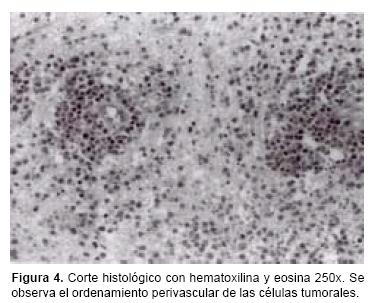

Los estudios histopatológicos han demostrado que los LPSNC en pacientes IC son muy similares a los que se presentan en los pacientes VIH–positivos. Con microscopia a menor aumento se demuestra el patrón de infiltración angiocéntrico, formándose collares de células tumorales alrededor de los pequeños vasos sanguíneos con diferentes cantidades de depósitos de reticulina.14 En casos avanzados se llega a perder este ordenamiento perivascular y las células tienden a invadir el parénquima cerebral circundante, ya sea en forma de compactos agregados o como una infiltración difusa de células tumorales similar a la encefalitis.15 Se ha informado con frecuencia reacción astrocítica que en ocasiones tiende a ser muy marcada,16 así como áreas de necrosis coagulativa. Todo esto explica el motivo por el cual con mucha frecuencia estas lesiones son confundidas en el estudio transoperatorio con astrocitomas, glioblastomas multiformes o metástasis.17

Los resultados de las biopsias realizadas por estereotaxia, mostraron que sólo en tres pacientes el diagnóstico histológico transoperatorio correspondió a linfoma, y en el resto fue confundido con astrocitomas, metástasis o glioblastomas multiformes. En el análisis de las biopsias por microscopia de luz a menor aumento fue posible observar un patrón de infiltración angiocéntrico, formando collares de células tumorales rodeando pequeños vasos cerebrales (Figura 4). Con mayor aumento fue posible observar con más detalle el cúmulo de células, en donde en algunos casos consistió en una combinación de células grandes y pequeñas pero persistiendo el ordenamiento perivascular (Figura 5). Sin embargo, en los pacientes con estadios más avanzados de la enfermedad se apreció pérdida del ordenamiento perivascular, con invasión de las células tumorales al parénquima cerebral. También se observó reacción astrocítica asociada, además de la presencia de macrófagos. La mayoría de los tumores fueron considerados de la variedad de células grandes difusas, de acuerdo a la Clasificación Revisada Europea–Americana de Linfoma (REAL),27 y en un solo caso correspondió a la variedad anaplásica. Por inmuhistoquímica, el total de los tumores resultaron positivos a los antígenos CD20 y CD79A, por lo que se consideraron de células B.